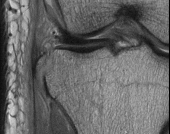

A 65-year-old male presents with classic symptoms of neurogenic claudication. He reports bilateral leg pain and fatigue that worsens with walking but is reliably relieved by leaning forward onto a shopping cart. In the pathogenesis of degenerative lumbar spinal stenosis, which structure is primarily responsible for dynamic central canal compression during spinal extension?

Correct Answer: Ligamentum flavum

Explanation:

In degenerative lumbar spinal stenosis, extension of the spine decreases the sagittal diameter of the canal because the ligamentum flavum buckles inward (shingling), dynamically compressing the thecal sac. Flexion of the spine pulls the ligamentum flavum taut, increasing the available canal space and alleviating neurogenic claudication symptoms. Hypertrophic ligamentum flavum is a major structural contributor to central stenosis.